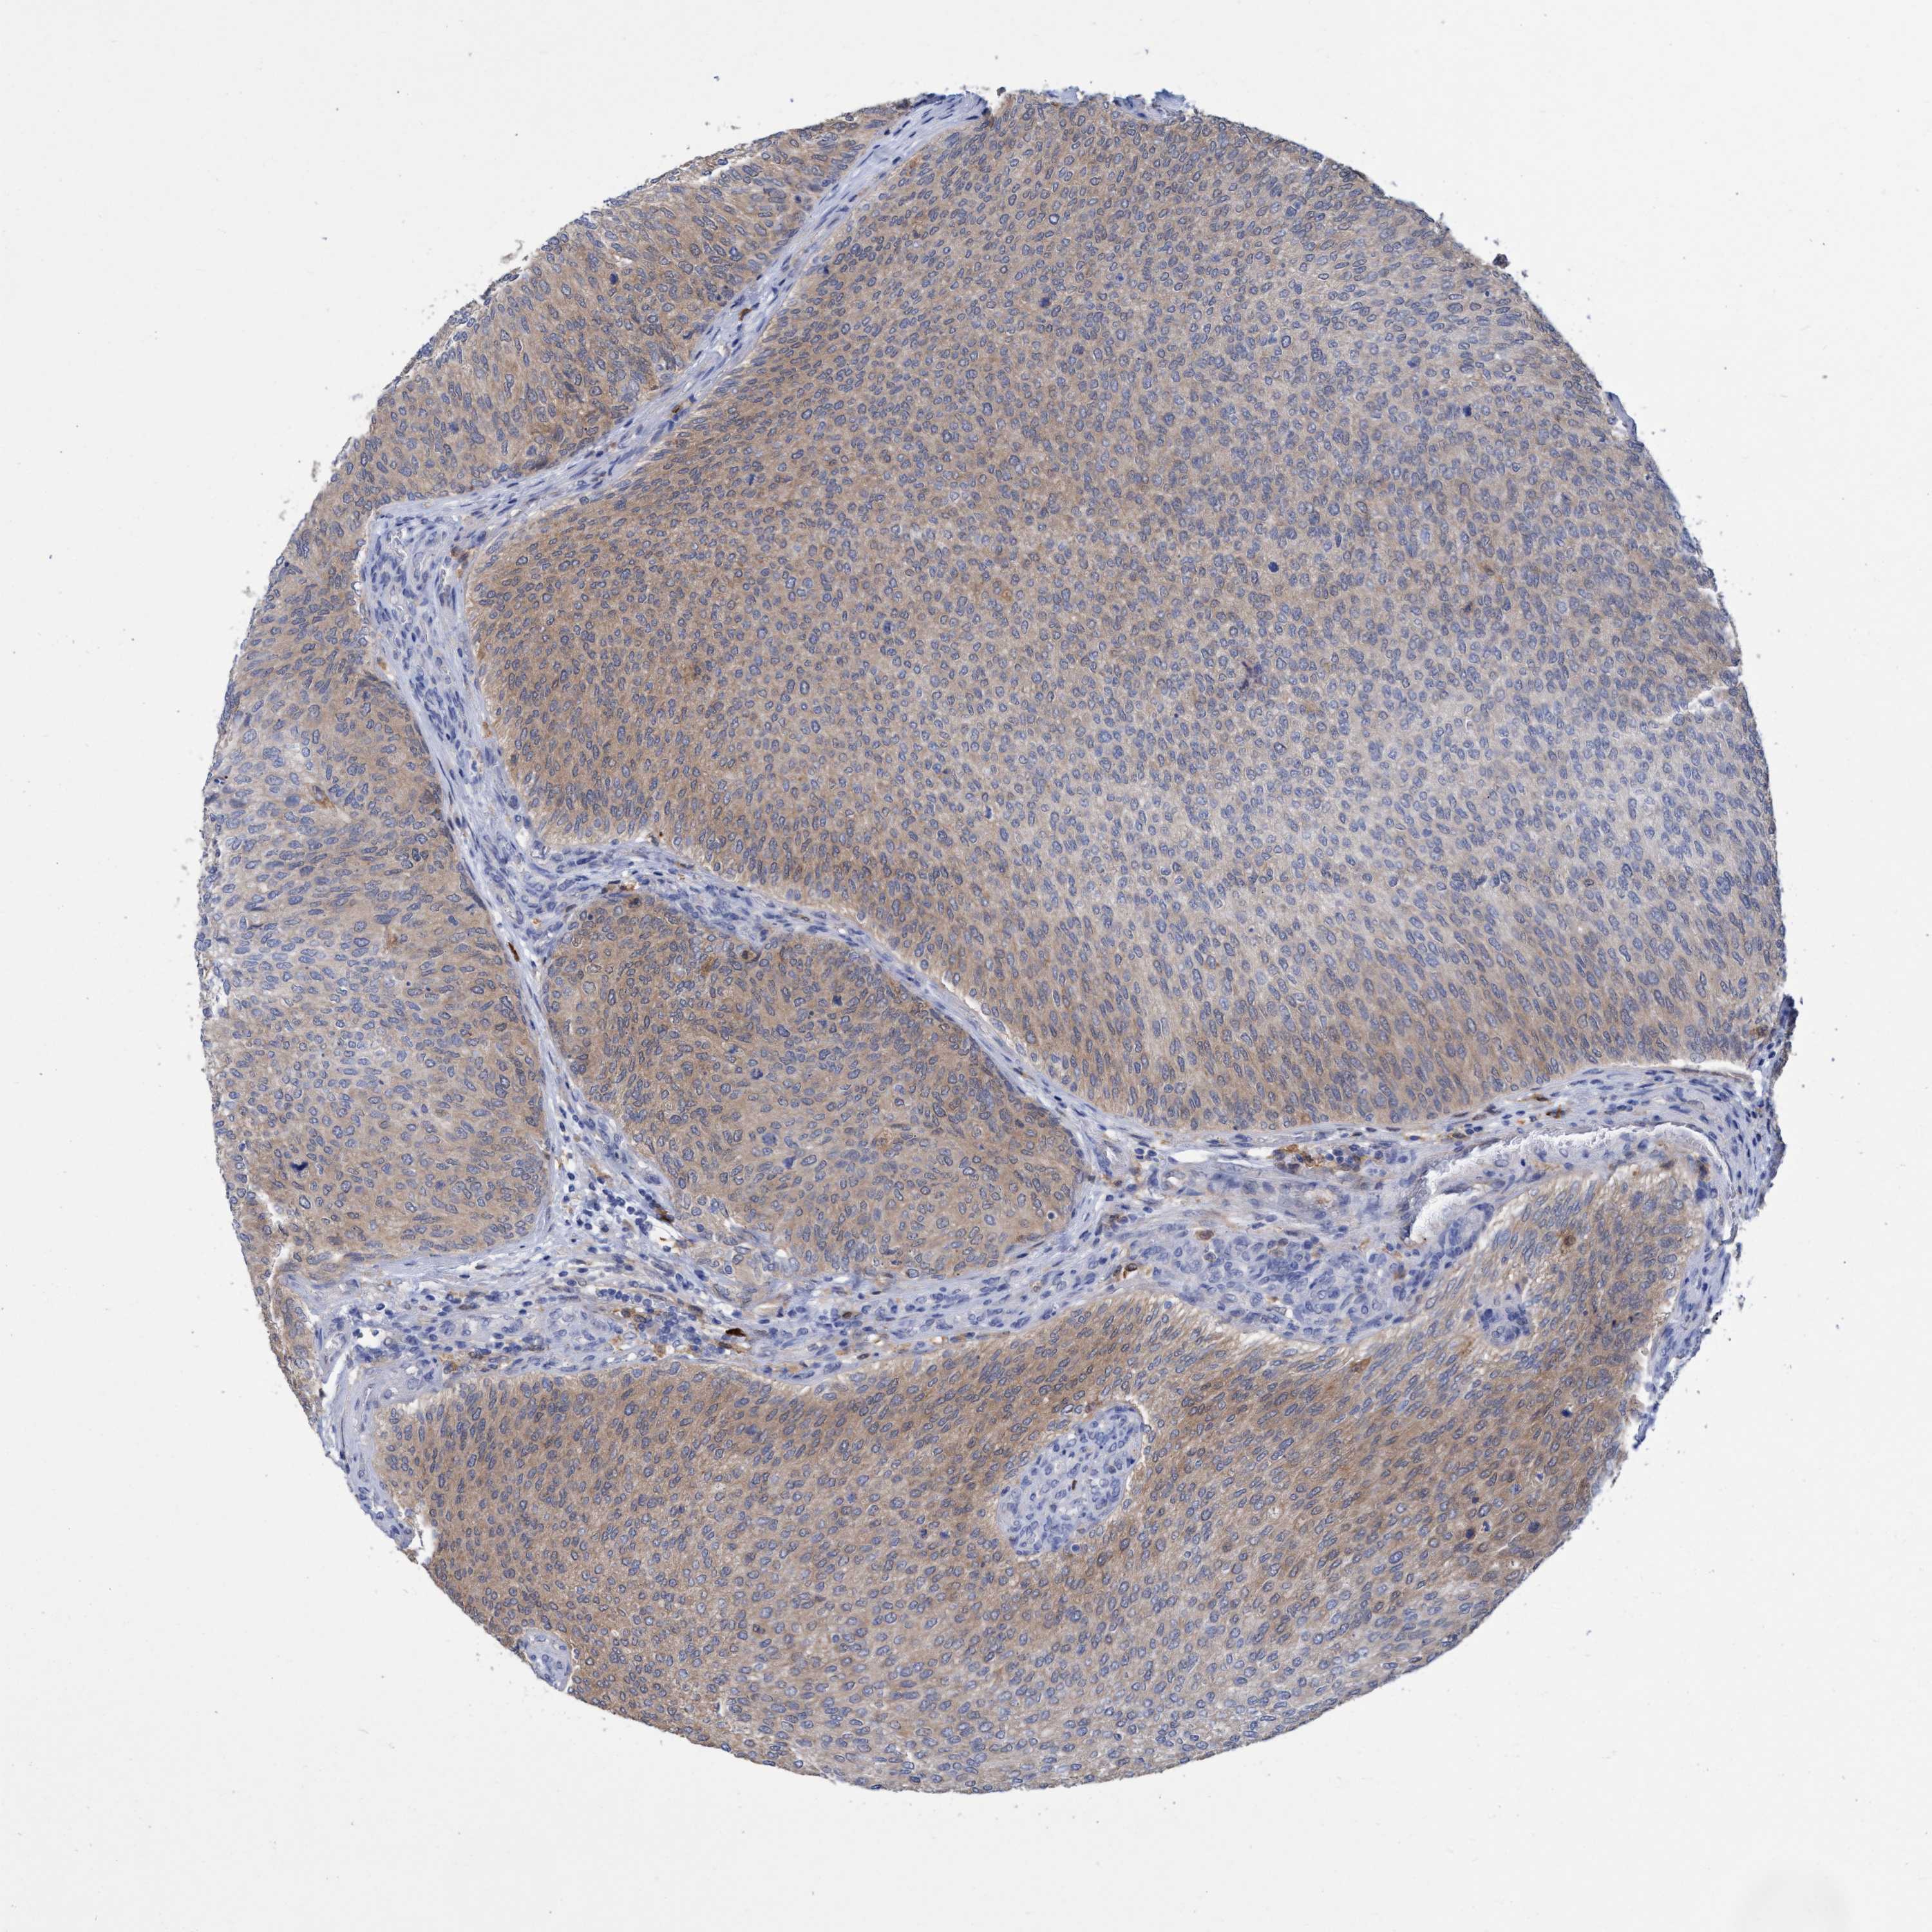

UROTHELIAL CANCER - Protein expressioni

A mouse-over function shows sample information and annotation data. Click on an image to view it in a full screen mode. Samples can be filtered based on level of antibody staining by selecting one or several of the following categories: high, medium, low and not detected. The assay and annotation is described here.

Note that samples used for immunohistochemistry by the Human Protein Atlas do not correspond to samples in the TCGA dataset.

Antibody stainingi

Antibody staining in the annotated cell types in the current human tissue is reported as not detected, low, medium, or high, based on conventional immunohistochemistry profiling in selected tissues. This score is based on the combination of the staining intensity and fraction of stained cells.

Each image is clickable and will lead to virtual microscopy that enables deeper exploration of all samples and also displays staining intensity scores, fraction scores and subcellular localization as well as patient and tissue information for each sample.

Antibody HPA023204

Antibody HPA027776

Urothelial carcinoma, Low grade

Urothelial carcinoma, High grade